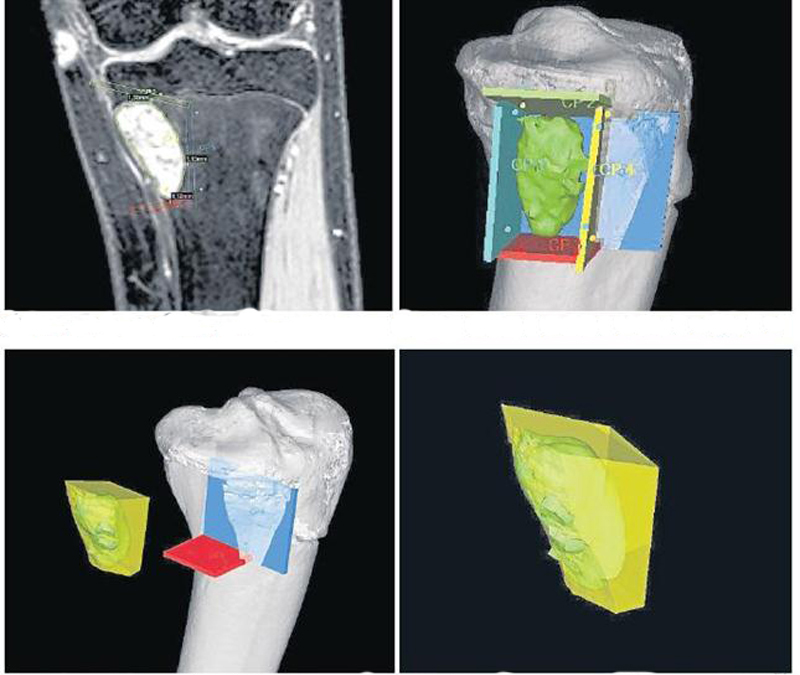

Utilizando un escenario de realidad virtual, desarrollado en Argentina, los equipos médicos del Hospital Italiano y el Instituto Tecnológico ubicados en Buenos Aires realizan una simulación interactiva y tridimensional de la afección para reemplazar la planificación prequirúrgica convencional.

El sistema es capaz de combinar imágenes realizadas por tomografía computada y resonancia magnética para obtener un detalle preciso del tumor que es preciso operar. So, el cirujano ensaya en un entorno virtual cómo será la intervención, definiendo las características del tumor, planificando los pasos a seguir y, if necessary, seleccionar de un banco de huesos de donantes lo que se precisa reconstruir.

Cuando llega el momento de la intervención, el cirujano dispone de un navegador quirúrgico, que contiene la cartografía de la zona a tratar, para llevar a cabo el proceso que ya ensayó con anterioridad. Esto aporta a la cirugía una mayor precisión y seguridad, evitando muchos riesgos.

Este sistema cambia por completo el paradigma de la cirugía. Mientras las intervenciones se planifican habitualmente con imágenes bidimensionales, esta solución permite planificar y ejecutar la cirugía en tres dimensiones. Por lo menos en tejidos rígidos, como los huesos o la corteza cerebral (in this case, sólo si se trata de un tumor que no cambiará de posición ni de forma).